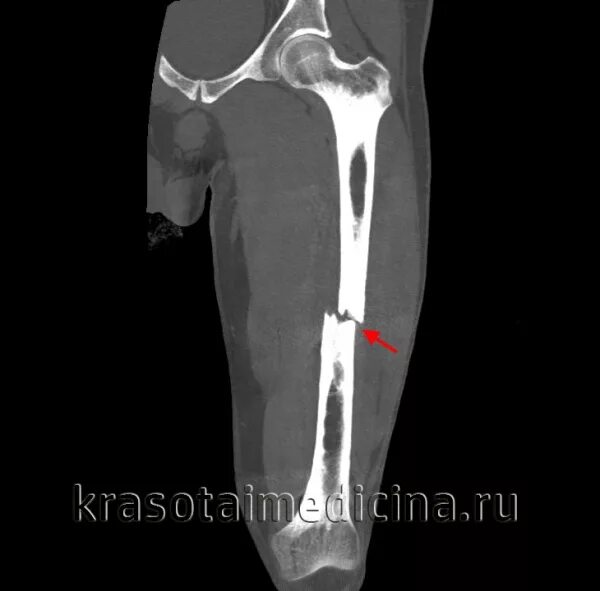

Перелом 1 3 бедра